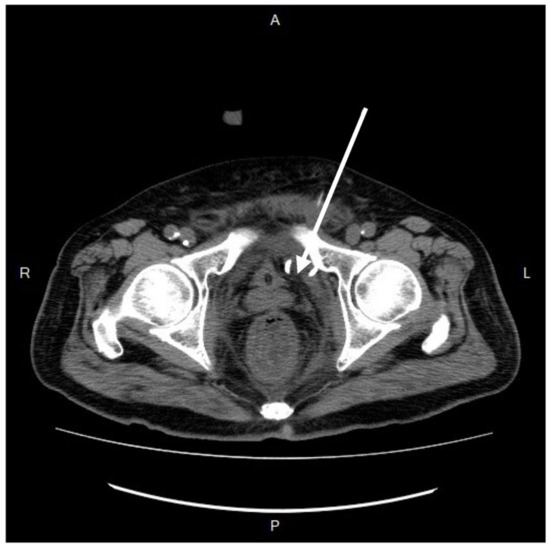

Further diagnostic measures included a plain abdominal radiograph, which showed no pneumoperitoneum or abnormal fluid accumulation. Laboratory findings consisted of an elevated white blood cell count and C-reactive protein level (white blood cells: 27,830/μL; neutrophils: 90.6%; C-reactive protein: 21.65 mg/L). Abdominal contrast-enhanced computed tomography (CT) showed a heterogenous fluid-filled perianal abscess measuring 5.0 × 4.4 × 6.8 cm (Figure 1) in the left perianal region, with extraperitoneal air spreading through the abdominal wall fascia (Figure 2 and Figure 3). The primary abscess was situated in the supra-levator space, potentially involving the levator muscle (infra-levator), as indicated by its migration from the perianal level to the extraperitoneal level. After a comprehensive review of the patient’s symptoms, medical history, age, and current status, immediate arrangements for endoscopic tests, including upper gastrointestinal endoscopy and colonoscopy, were not made. Additionally, gastrointestinal tract specimens, such as fecal samples for calprotectin and lactoferrin, were not collected, thereby not suggesting the likelihood of inflammatory bowel diseases.

Figure 1. Coronal view of contrast-enhanced computed tomography. A hypo-attenuated area (size: 5.0 × 4.4 × 6.8 cm) on the left side perianal, with spotted air and irregular contour (arrow). The abscess cavity showed contralateral extension to the supra-sphincteric direction (red arrow). R, right; L, left; H, superior; F, inferior.